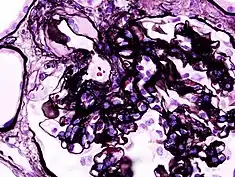

_HE.jpg.webp)